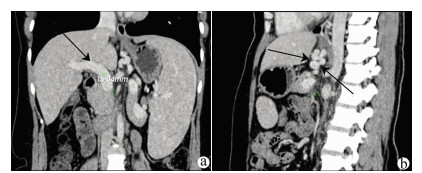

A case of idiopathic portal hypertension in chronic hepatitis B

CAI MX, LIN LW, XUE ES, et al. Color Doppler in the diagnosis of idiopathic portal hypertension and its clinical value[J]. J Clin Hepatol, 2009, 25(5): 374-376. http://lcgdbzz.org/article/id/LCGD200905023

蔡敏娴, 林礼务, 薛恩生, 等. 特发性门静脉高压症的彩色多普勒超声诊断与临床价值[J]. 临床肝胆病杂志, 2009, 25(5): 374-376. http://lcgdbzz.org/article/id/LCGD200905023